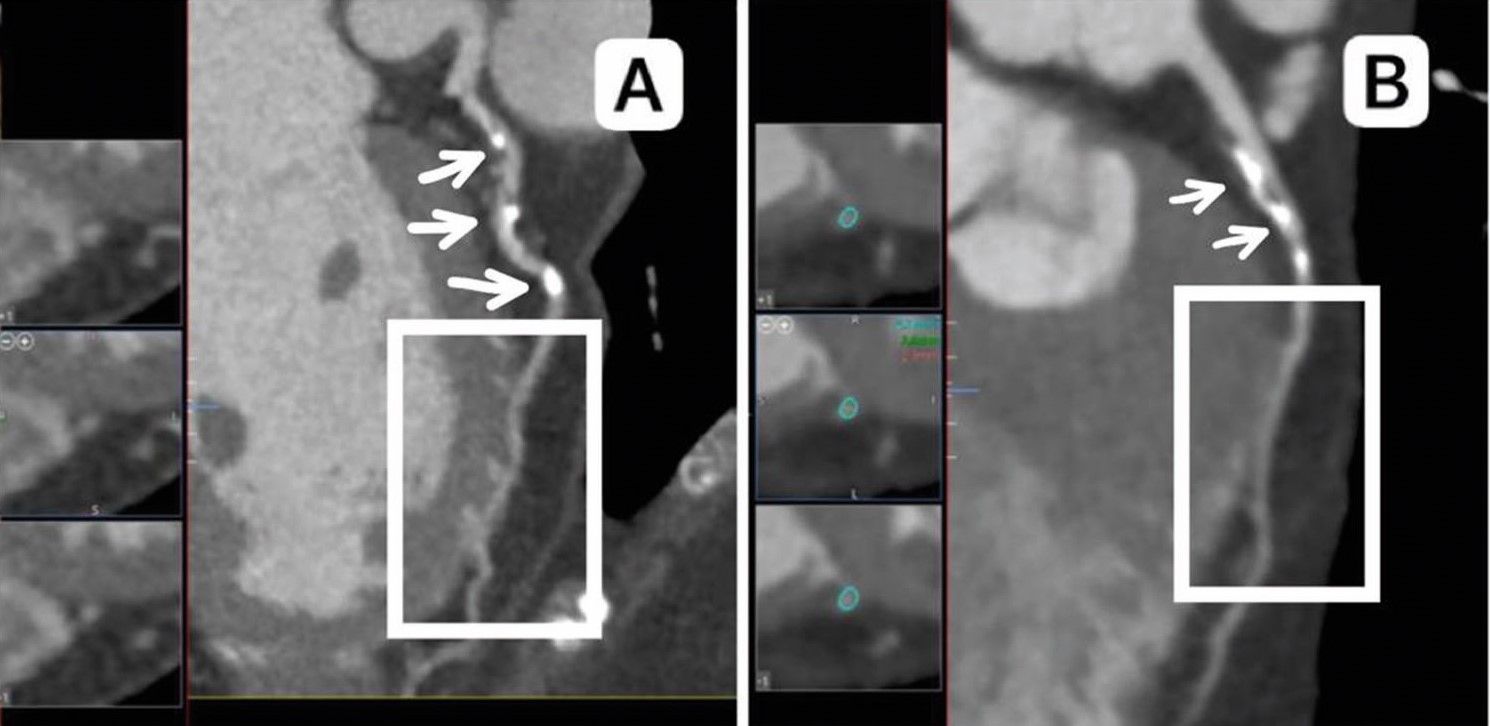

Диагностическим симптомом ММ является «эффект доения» и/или феномен «шаг вниз – шаг вверх», вызванный сокращением мышцы в систолу. Стоит отметить, что КАГ коронарных артерий (КА) является «золотым стандартом», например, при диагностике гемодинамически значимых стенозов венечных артерий или шунтографии. Она имеет некоторые технические ограничения по сравнению с другими новыми методами визуализации, такими как внутрисосудистое ультразвуковое исследование и мультиспиральная компьютерная томографическая коронарная ангиография (КТ-КАГ). Проведение КТ-КАГ позволяет лучше визуализировать ММ – от 26,6% [3] до 73% [4] случаев. Компьютерная томография определяет ММ как фрагмент артерии, который частично или полностью окружен миокардом. Последние разработки, позволяющие выполнять функциональную оценку, дополнительно повышают диагностическую ценность КТ-КАГ для выявления гемодинамически значимых ММ (рисунок 2).

Рисунок 2. Туннелированный фрагмент и выраженный миокардиальный мостик (стрелки) в систолу (А) и диастолу (В) в проксимальном сегменте ПМЖВ (КТ-КАГ).

Figure 2. A tunneled fragment and a pronounced myocardial bridge (arrows) in the systole (A) and diastole (B) in the proximal segment of the LAD (CT angiography of the coronary arteries).